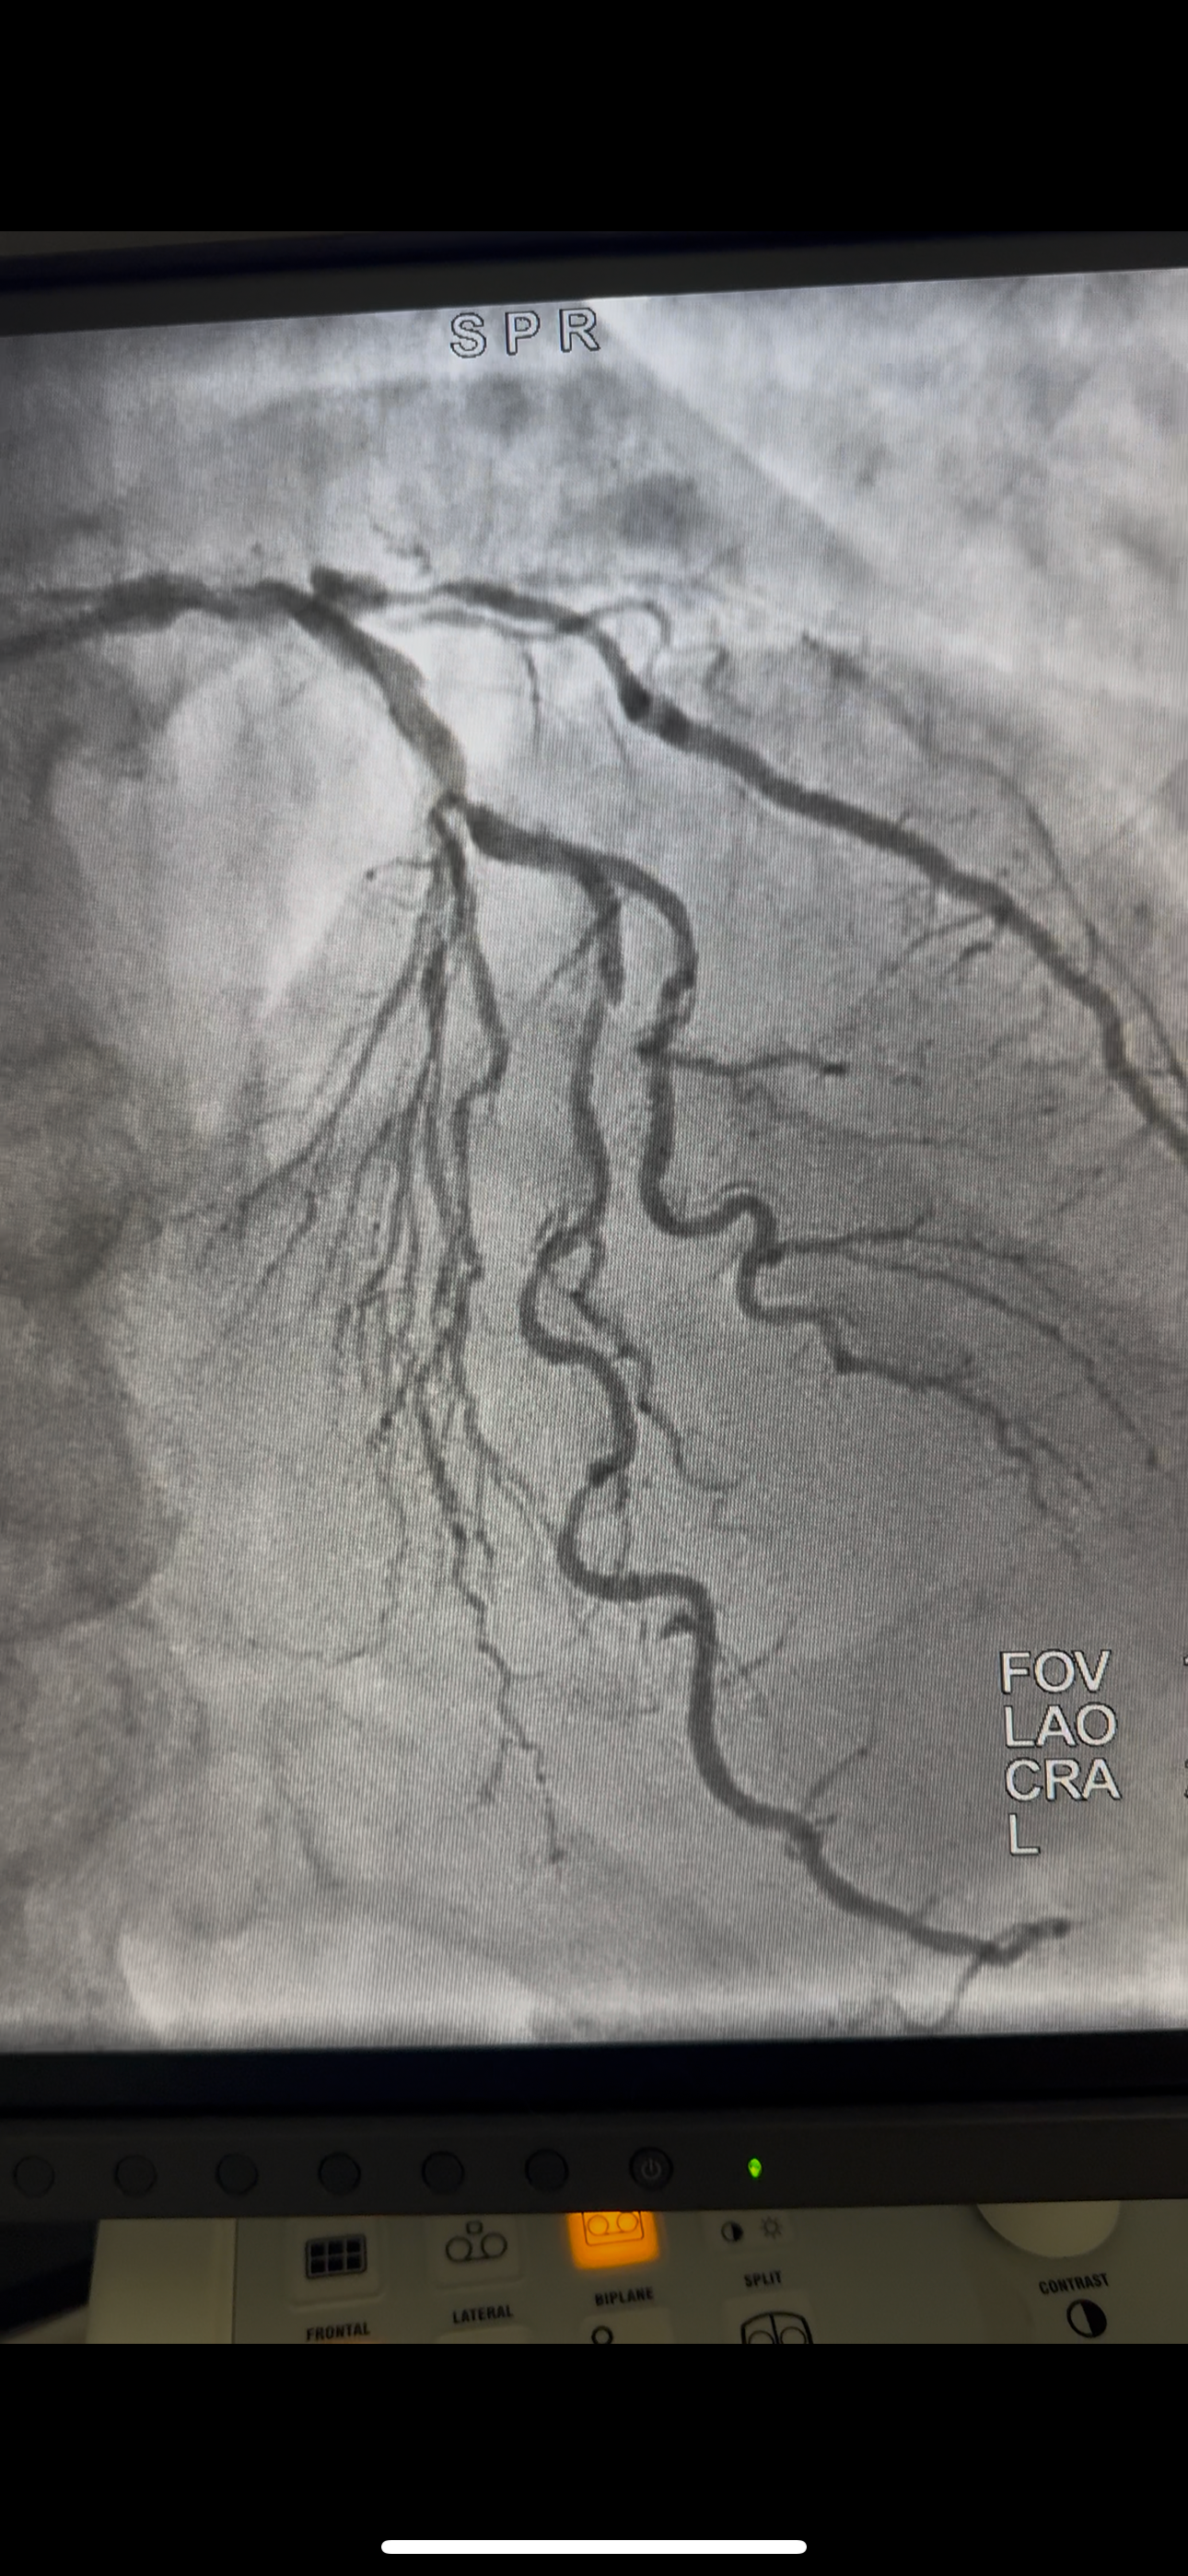

Hola a todos, espero que se encuentren bien. Quiero pedir su apoyo de corazón, ya que mi papá se sometio una cirugía a corazón abierto. Fue un procedimiento urgente y los gastos hospitalarios son muy elevados.